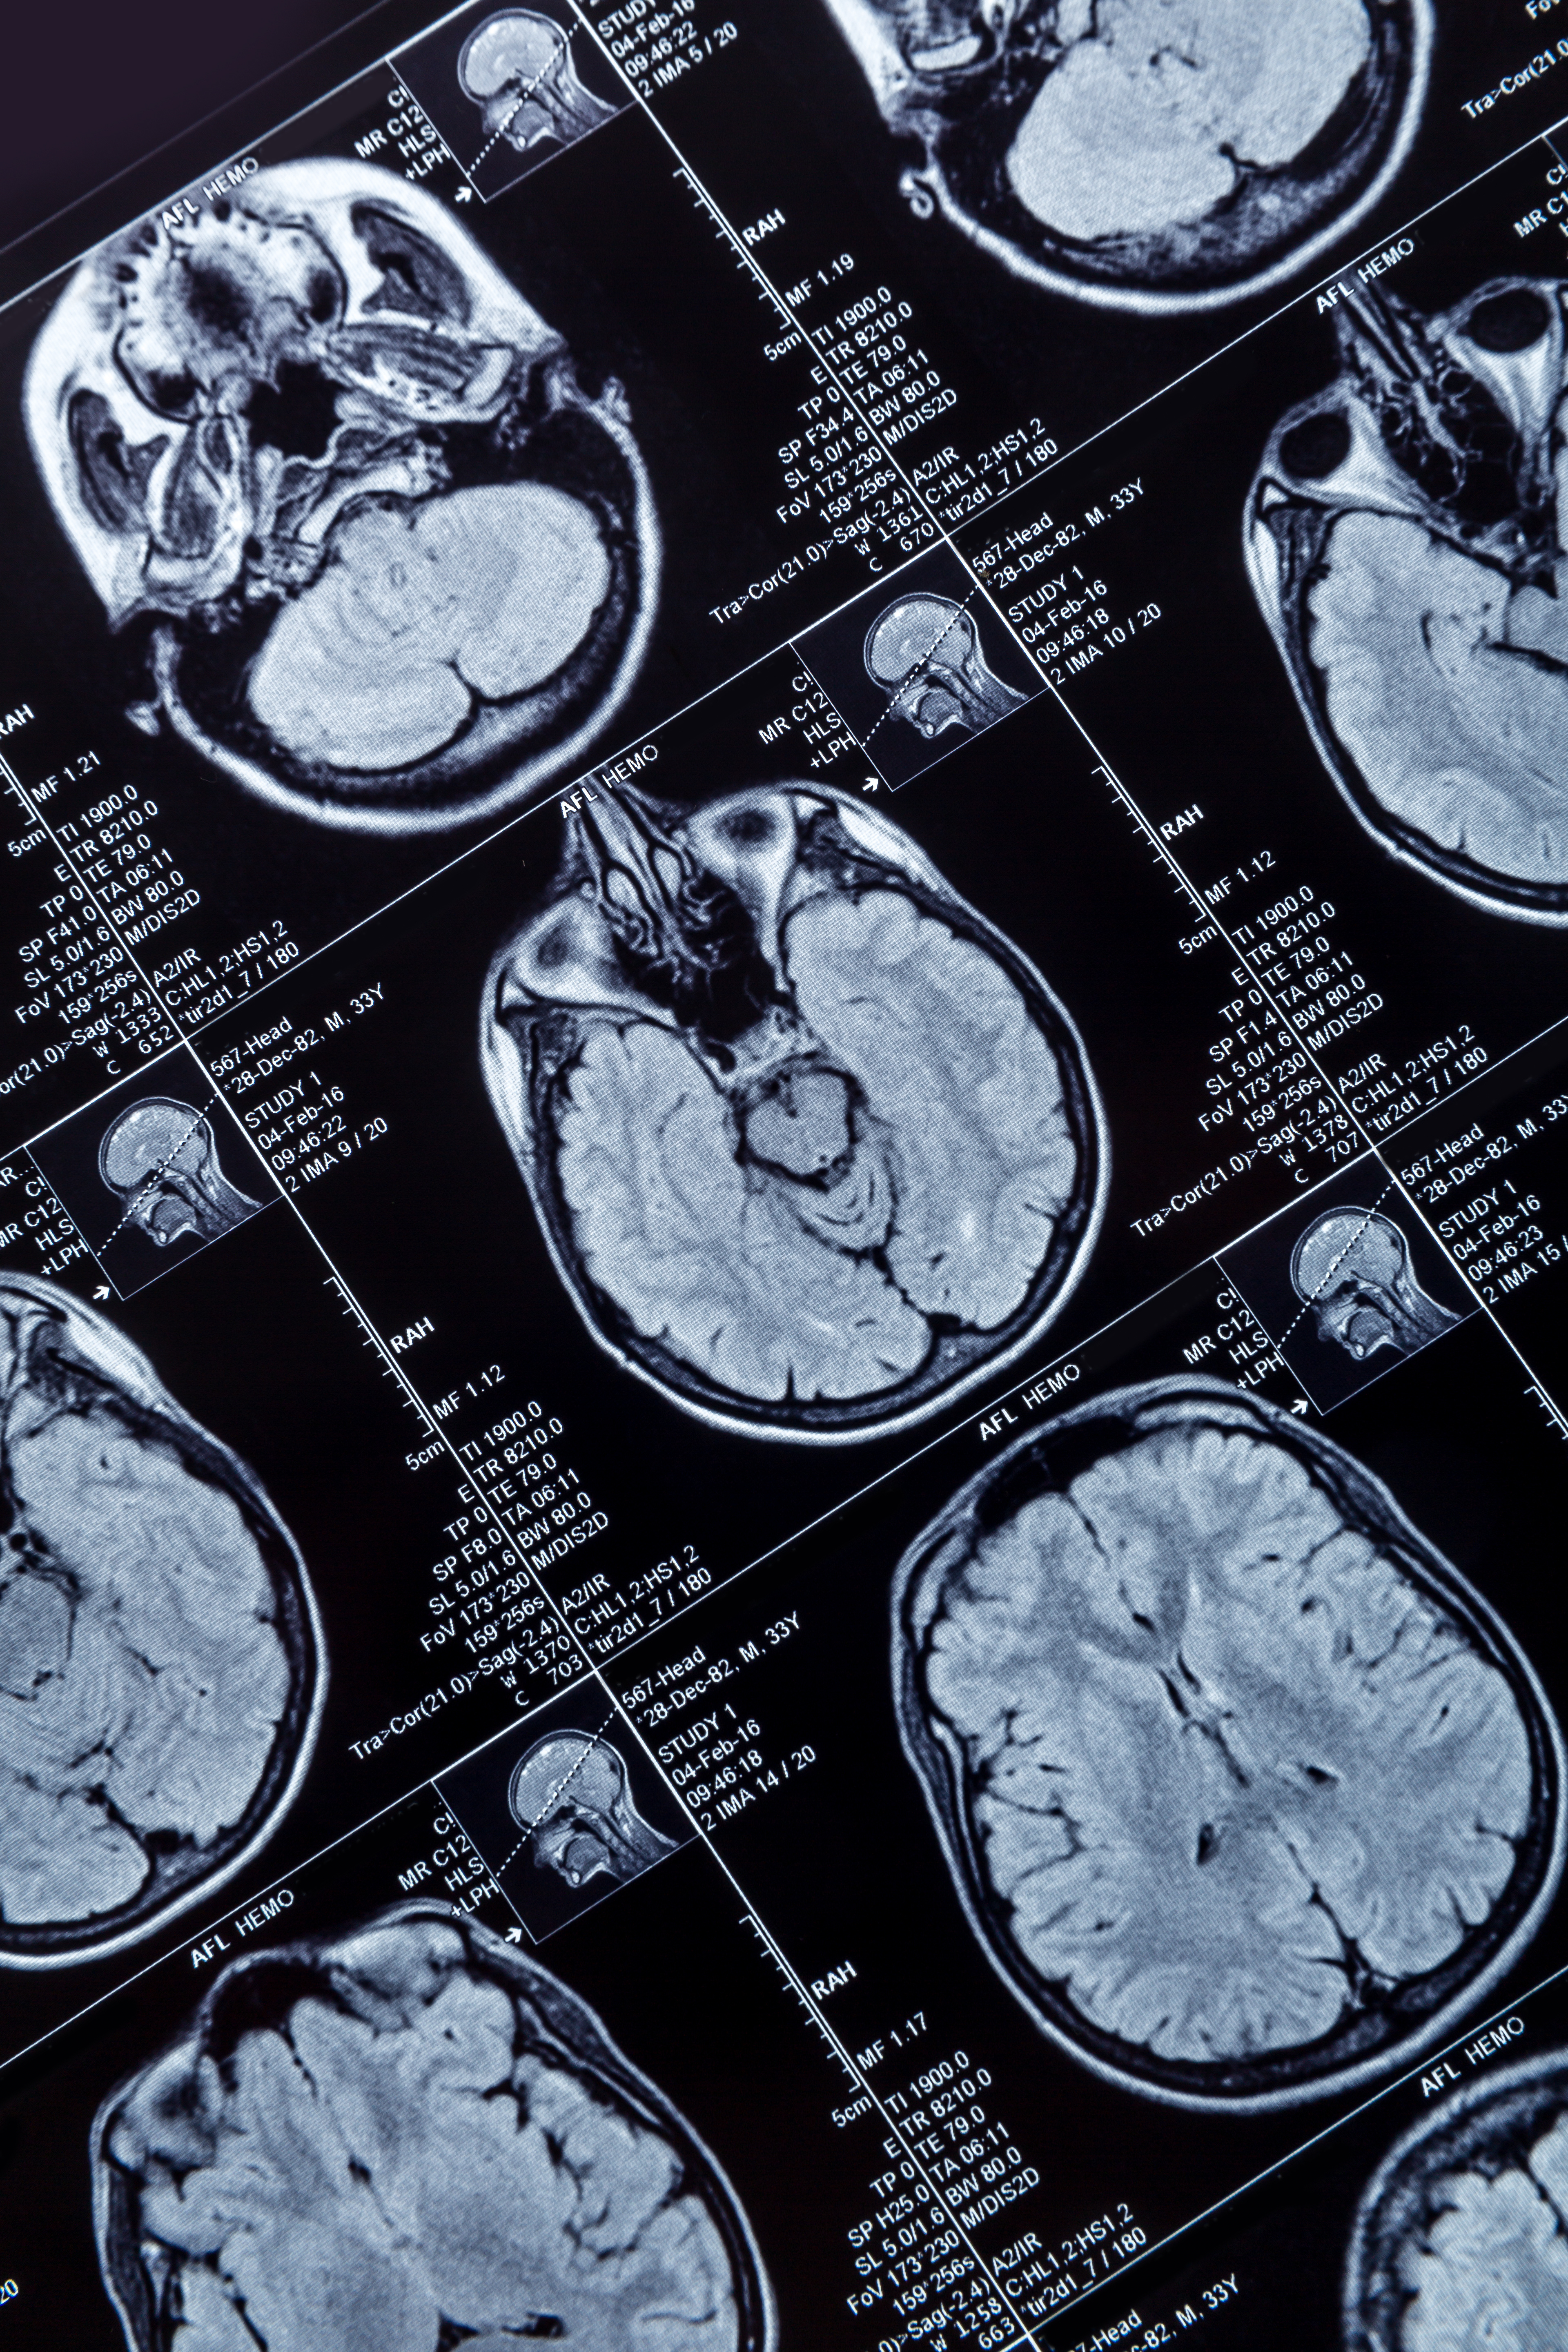

MRI shows that women who have their ovaries removed before menopause have reduced white matter integrity in multiple regions of the brain later in life, according to research published June 20 in Alzheimer’s & Dementia.

Mielke et al studied the impact of PBO overall and PBO on the intensity of white matter, the nerve fibers that connect neurons in different areas of the brain. The researchers used MRI diffusion tensor imaging (DTI), which generates images from the diffusion of water molecules to generate contrast in images. They obtained MR brain images on a 3-tesla scanner with an eight-channel phase array coil between 2011 and 2020 and acquired DTI scans using a single-shot echo-planar imaging sequence with an isotropic resolution of 2.7 mm.